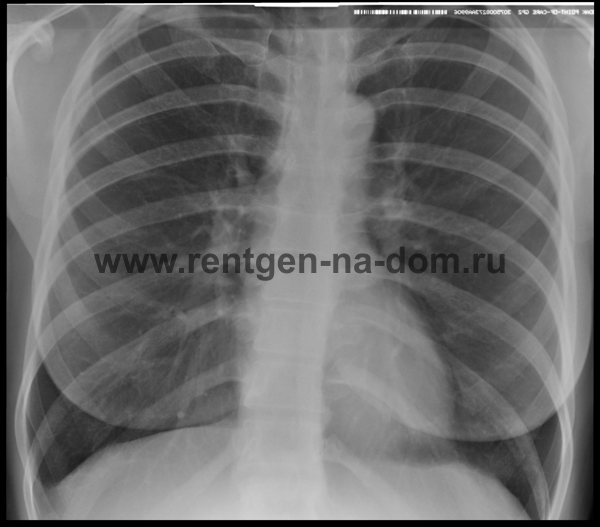

Рентгенограмма легких - норма и патология (на цифровом рентгеновском снимке) 11 .11 .2014 03 .04 .2015 Александр 1 Комментарий

На вышеприведенном фото рентгенограммы выполнены одному и тому же человеку в положении стоя (а) и лежа (б) . . . . На снимках легких, выполненных у одного человека, можно было наблюдать различие . . .